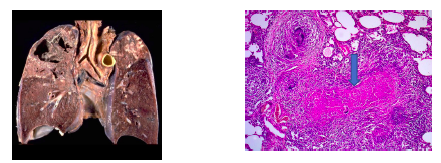

What is the likely pathology? Explain findings of gross specimen and histo slide

mycobacterial infection

Gross specimen = cavitations in R upper lobe (most common area for TB infection)

histology slide = granuloma with caseaous necrosis (cheese-like cell death - most commonly associated with TB infection)